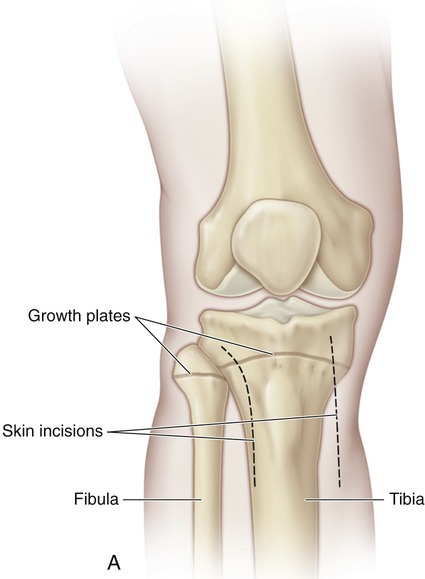

Анатомия фибулы: Подробные фотографии и схемы